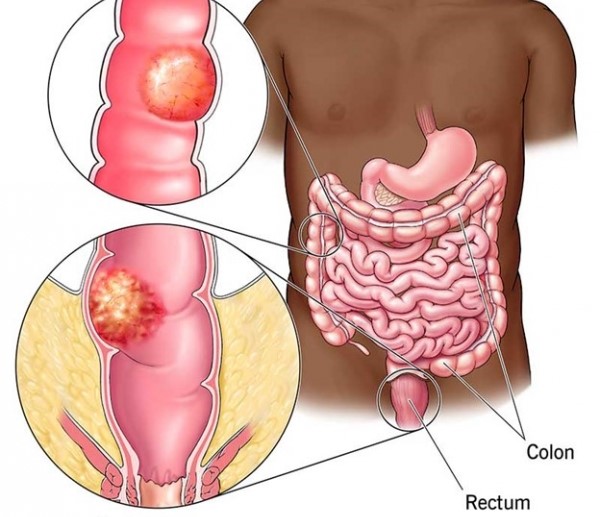

قیمت: 68٬000 تومان - دسته بندی فایل: پاورپوینتپاورپوینت بیماریهای مقعد و راست روده

فروش ویژه پاورپوینت حرفه ای بیماریهای مقعد و راست روده با تخفیف استثنایی فقط 72384 هزار تومان تعداد اسلاید: 39 اسلاید